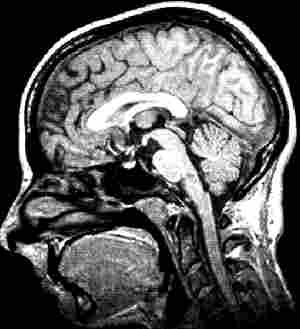

NMR und PET

VIII: Darstellung des Gehirns butmeth.jpg

NMR: Kernspintomographie

nmrin.jpg petin.jpg